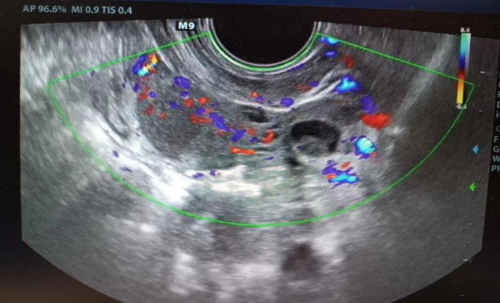

(南华大学附属长沙中心医院)就诊,入院时由于腹痛剧烈,小雨已经无法正常行走。完善经直肠盆腔彩超后,提其左侧输卵管积液,左侧附件区类“漩涡”样回声,疑输卵管发生扭转,小雨马上被收入妇科住院。

接诊医生廖年春与患儿家长积极沟通并取得其同意后,第一时间为小雨行全麻下“腹腔镜探查术”。术中发现左侧输卵管积液、增粗,直径约5cm,扭转5圈,相当于扭转了1800°,其远端呈暗红色缺血缺氧表现,幸亏入院及时,不然有可能发生输卵管缺血坏死!手术医生将扭转的左侧输卵管进行复位,恢复正常血运,并对输卵管进行修复,完好地保留住了附件。术后,小雨没再出现腹痛的情况,3天后痊愈出院。